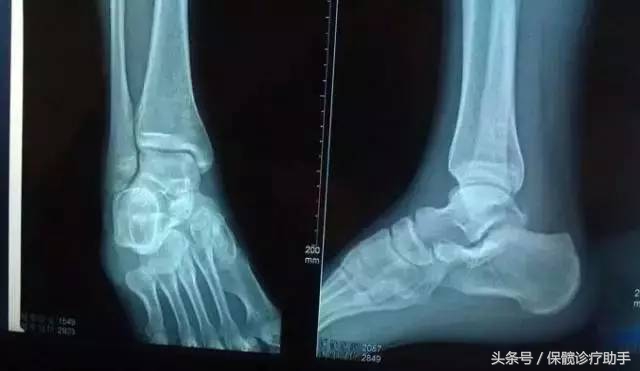

关键词4:踝关节的距骨缺血性坏死

病理特征:

距骨在踝关节内侧,处于踝关节囊中,就像踝关节的轴承一样。人的两个踝关节就像承重墙,承担着人体的重量,极易发生扭伤。而距骨又没有肌肉附着,只有与踝关节关节囊相连的地方有一条血管为它供血,如果踝关节扭伤伤到距骨的供血血管,就会直接影响距骨的供血,没有供血,缺乏营养供应,时间久了就会发生距骨缺血性骨坏死。

一般的踝关节扭伤只会导致韧带扭伤或者内外踝骨折等,很少能伤及距骨,只有高空坠落等力量较大的撞击可能伤及距骨。尽管距骨不容易受伤,但受伤后很容易被疏忽。

主要表现:

踝关节僵硬、活动不灵活,行动疼痛。